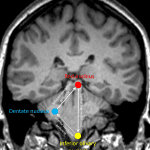

Initial MRI

- Relatively symmetric, minimally expansile T2/FLAIR signal hyperintensity in the midbrain and pons (predominantly involving the corticospinal and central tegmental tracts with sparing of the transverse pontine fibers) extending superiorly into the right greater than left internal capsules. There is also involvement of the left superior cerebellar peduncle

- No corresponding enhancement, restricted diffusion, or susceptibility artifact

Hypertrophic olivary degeneration (HOD)